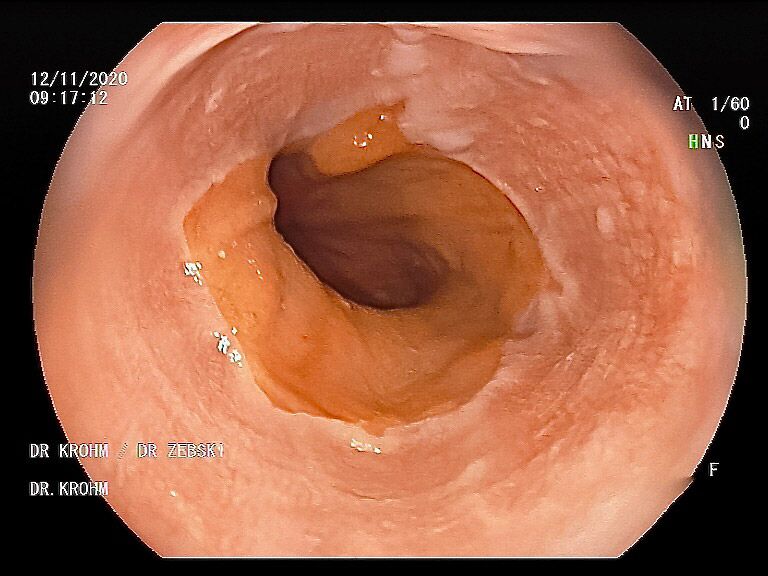

Die Gastroskopie (Magenspiegelung) hat sich als sicheres Standardverfahren zur Beurteilung des oberen Verdaungstraktes bei vielfältigen Krankheitsbildern und Fragestellungen fest etabliert.

Mit einer Gastroskopie werden Speiseröhre, Magen und Zwölfingerdarm (der oberste Teil des Dünndarms) untersucht. Dazu wird ein geschmeidig biegsames, schlankes Endoskop mit eingebauter Digitalkamera durch den Mund eingeführt. Minimalste Veränderungen können dabei gesehen werden, die im Röntgenbild oder einer Kernspintomographie (MRT) noch gar nicht erkannt werden. Im Vergleich zu anderen bildgebenden Untersuchungsverfahren ist bei der Endoskopie neben der wichtigen optischen Beurteilung auch die sofortige Möglichkeit gegeben, Gewebeproben aus auffälligen Bereichen zu entnehmen. Dazu wird eine kleine Spezialzange durch einen Kanal im Endoskop geschoben und die Probe ganz präzise aus dem entsprechenden Gewebe gewonnen. Da die Schleimhäute schmerzunempfindlich sind, spüren Sie davon nichts. Die Proben werden von Spezialisten mikroskopisch untersucht und ermöglichen dann eine zielgerichtete Therapie; zum Beispiel wenn eine Magenschleimhautentzündung durch eine chronische Infektion ausgelöst wird, die mit einer Antibiotikakur erfolgreich behandelt werden kann.